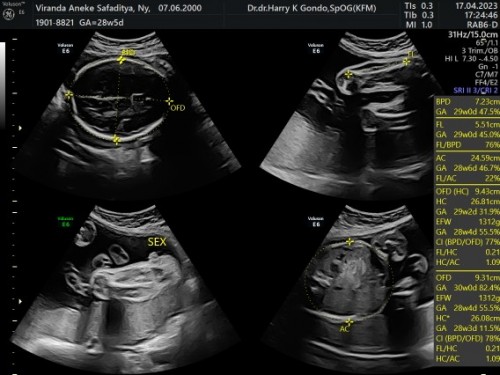

Baby Boy/Girl ya. Bantu jawab dong?

Mau tanya dong ini baby boy/girl. Soalnya gak jelas gitu thankuou

Kayanya emang perempuan deh disela2 antara selangkangan kaki kalau laki2 itu keliatan jelas kalau ada burungnya apalagi kalau 28week itu testisnya pun sudah turun dan jelas sekali.

dokternya bilang cewek, tp masih kuramg yakin aja gitu Bun

itu ada penisnya, laki kayanya